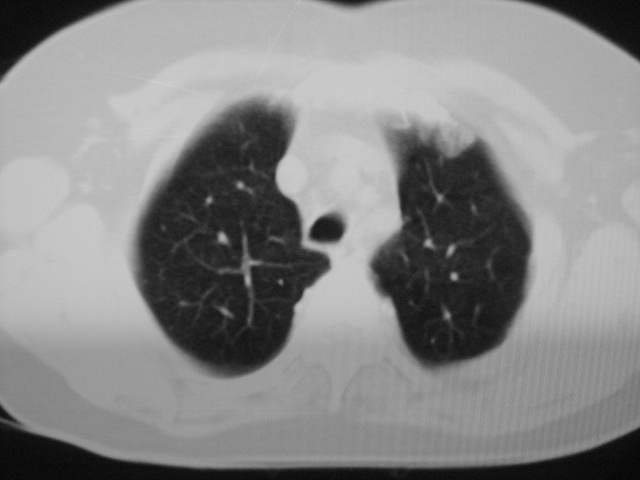

以下是引用清清楚楚在2007-8-28 7:13:00的发言:[br]右肺下叶可见斑片状高密度影,边缘模糊;右肺中叶内侧段及左肺舌段亦可见小斑片状模糊影。[br]考虑双肺感染,建议抗炎治疗后复查。

以下是引用天南地北在2007-8-27 23:49:00的发言:[br]右肺下叶可见斑片状高密度影,边缘模糊;右肺中叶内侧段及左肺舌段亦可见小斑片状模糊影。[br]考虑双肺感染,建议积极抗炎治疗后复查。

以下是引用天南地北在2007-8-27 23:49:00的发言:[br]右肺下叶可见斑片状高密度影,边缘模糊;右肺中叶内侧段及左肺舌段亦可见小斑片状模糊影。[br]考虑双肺感染,建议抗炎治疗后复查。

以下是引用难听在2007-8-28 13:17:00的发言:[br]右肺下叶背段支气管狭窄,是否可以考虑新生物伴阻塞性肺炎.请大家帮帮忙,这个病人是卫生局长的丈母娘.惹不起啊.